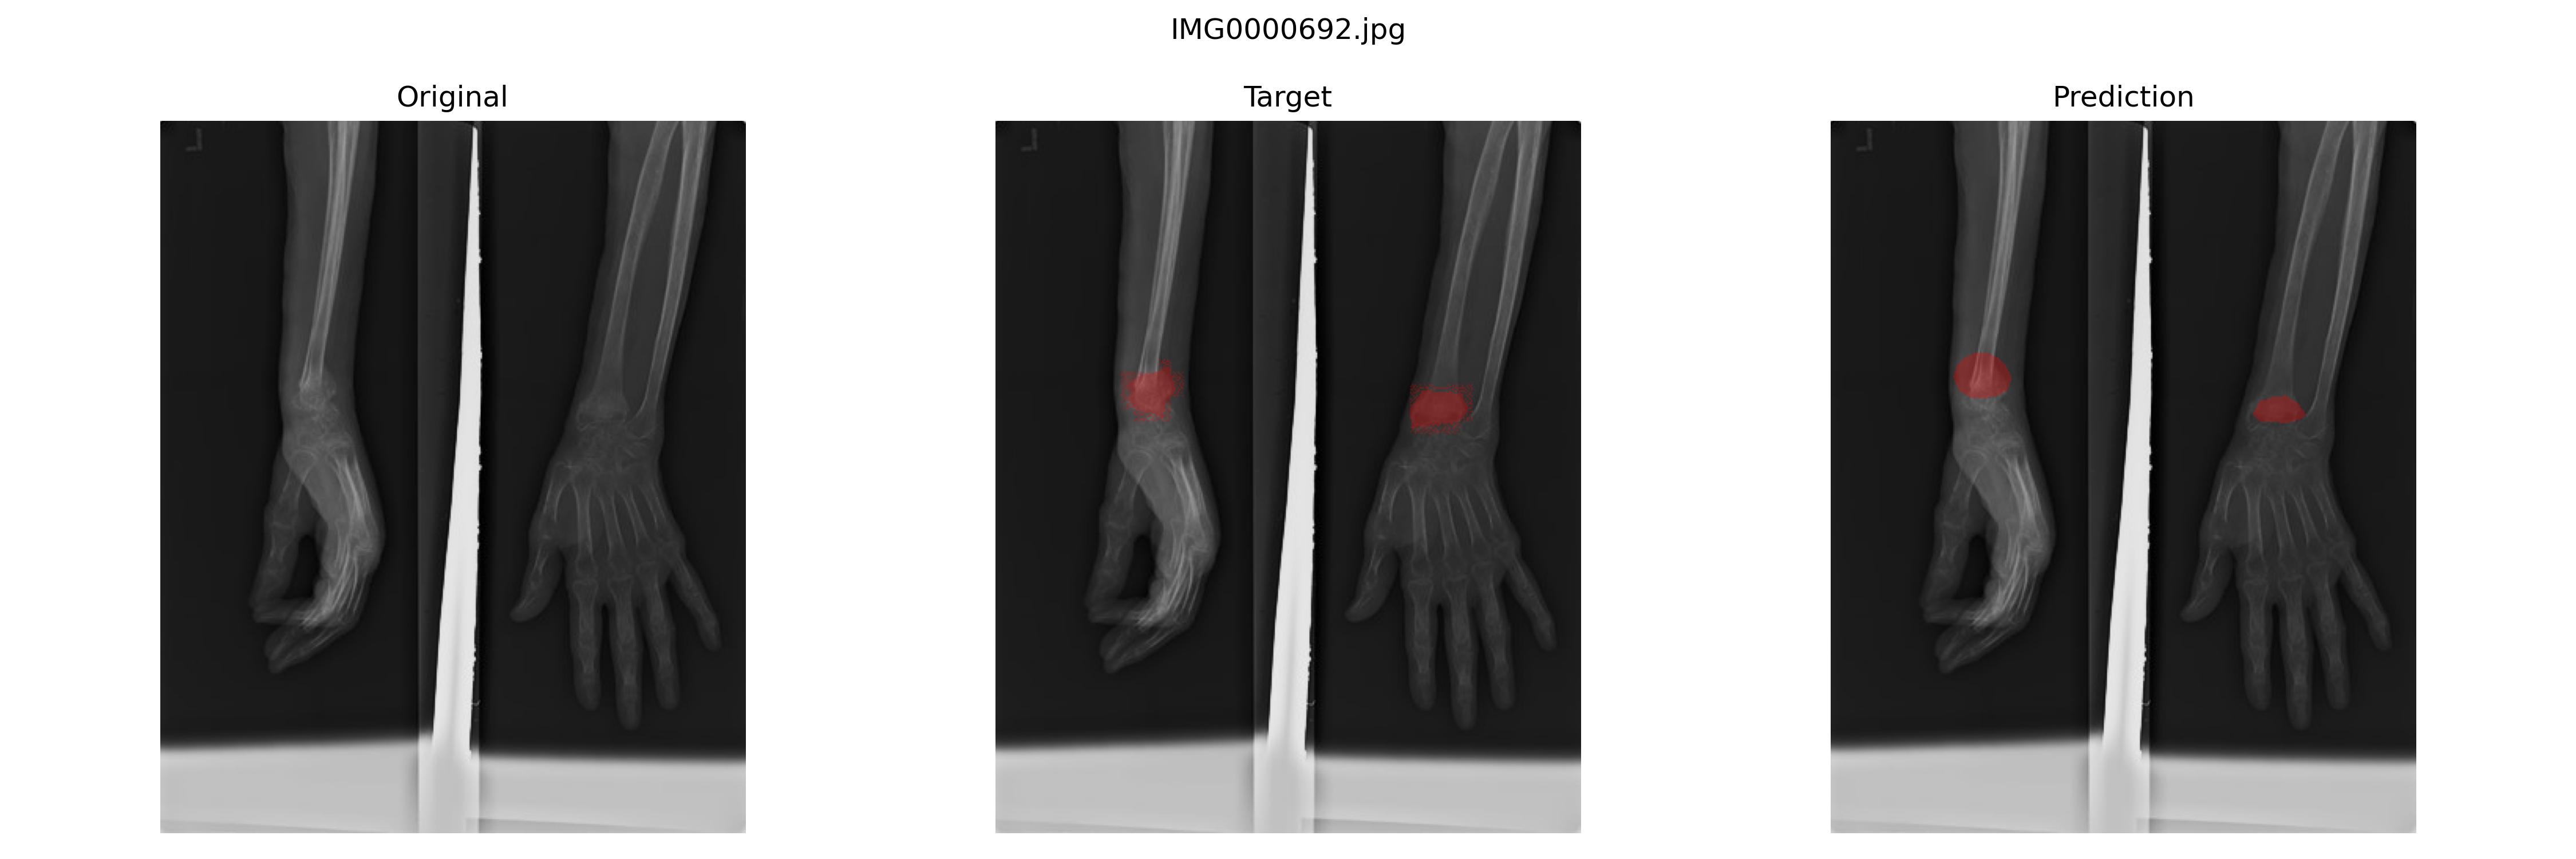

FCN

用相似的代码进行FCN的训练,最佳模型是

epoch:66,sensitivity(Recall):0.8410347542721659,specificity:0.984027932237679,precision:0.8603991908024482

结果预览

我感觉甚至可以说在一些地方,模型分割得比Ground Truth要好一些。